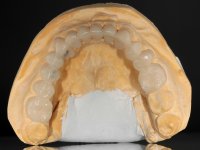

Paciente do sexo masculino, com 42 anos de idade, não fumador. Apresentava uma reabilitação metalo -cerâmica feita há mais de 10 anos com exposições radiculares e infiltrações. No maxilar superior apresentava uma coroa no 1.1,uma ponte de dois elementos no 2.1 e 2.2.e uma ponte de 4 elementos nos dentes 2.4,2.5,2.6 e 2.7 com o 2.6 como pôntico. Os dentes 1.6/1.5/1.4/1.3/1.2/1.1/2.1/2.2/2.3/2.4/2.5 e 2.7 apresentam tratamento endodôntico radical com o 2.4/2.5 e 2.7 a necessitarem de ser refeitos. No maxilar inferior apresentava uma ponte metalo-cerâmica de 4 elementos nos 4 incisivos e uma ponte de 3 elementos (3.3 e 3.4) com um dente supranumerário como pôntico. Os dentes 4.6/4.5 e 4.2 apresentavam tratamento endodôntico com o 4.2 a necessitar de ser refeito. Os dentes 4.3 e 4.4 apresentavam extensas cáries linguais com algum comprometimento mesial. As peças protéticas apresentavam-se infiltradas com exposição radicular associada. Apresentava uma D.V.O. diminuída e uma mordida cruzada lado direito. O paciente tinha uma satisfatória saúde periodontal e uma boa higiene oral.

Foi proposto ao paciente fazer uma reabilitação total com infraestruturas em zircónia revestidas a cerâmica. No maxilar superior, seriam realizadas 6 coroas (1.3/1.2/1.1/2.1/2.2/2.3), uma ponte de 3 elementos (1.4/1.5/1.6) e uma ponte de 4 elementos (2.4/2.5/2.6 e 2.7). No maxilar inferior, foram propostas 7 coroas (4.3/4.2/4.1/3.1/3.2/3.5 /3.6) e duas pontes (4.4//4.5/4.6) e (3.3/3.4#/3.4).O objetivo seria subir a D.V.O., descruzar a mordida do lado direito, eliminar as infiltrações e as exposições radiculares e reabilitar o paciente com estruturas protéticas com aspeto mais natural.

A primeira acção terapêutica foi tentar melhorar o tratamento endodôntico dos dentes (2.4/2.5/4.2)). A sua manutenção em boca seria condicionada pelo sucesso desta intervenção. Seguidamente foram feitas impressões em alginato e registo inter-maxilar em silicone para confeção em laboratório de uma ponte provisória em acrílico com reforço. O objetivo desta ponte provisória seria ensaiar o aumento da D.V.O. e descruzar a mordida do lado direito. Foi utilizado um monobloco de 13 dentes com o dente 2.6 com o pôntico. As coroas e as pontes foram removidas e os remanescentes coronários foram repreparados. A ponte provisória foi rebasada primeiramente com acrílico auto-polimerizável e de seguida com resina composta. Após 2 semanas de permanência em boca, foram feitas as impressões para confeção da ponte provisória inferior também realizada em laboratório. Especial cuidado foi colocado na remoção das coroas antigas, sendo feito primeiramente um corte axial que permitiu que fossem removidas de uma forma menos traumática. A temporização foi feita durante 8 semanas, permitindo que os tecidos gengivais estabilizassem posicionalmente. As impressões definitivas foram realizadas após afastamento gengival utilizando a técnica do fio único impregnado. Foi utilizada a técnica de dupla mistura com dupla viscosidade (putty soft e light).Simultaneamente foi realizada a recolha das relações inter-maxilares e o registo com arco facial. Foram confecçionados os modelos de trabalho e feita a sua correta montagem em articulador semi-ajustável. Em seguida foram feitas infra estruturas em zircónia que posteriormente foram revestidas por cerâmica. A prova de “biscoito” foi realizada em boca para avaliação estética e funcional sendo também avaliado o seu assentamento e ajuste. A reabilitação definitiva foi cimentada em boca utilizando um cimento de ionómero de vidro reforçado por resina.